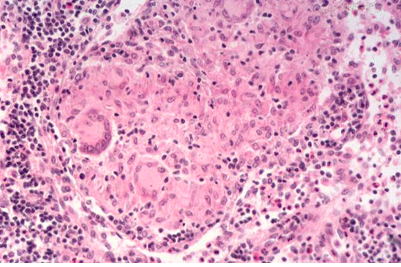

mucosal surface of the colon is hyperemic and is partially covered by a yellow-green exudate. The mucosa itself is not eroded. Broad spectrum antibiotic usage (such as clindamycin) and/or immunosuppression allows overgrowth of bacteria such as Clostridium difficile to cause this appearance.

Microscopically, the pseudomembrane is seen to be composed of inflammatory cells, necrotic epithelium, and mucus in which the overgrowth of microorganisms takes place. The underlying mucosa shows congested vessels, but is still intact